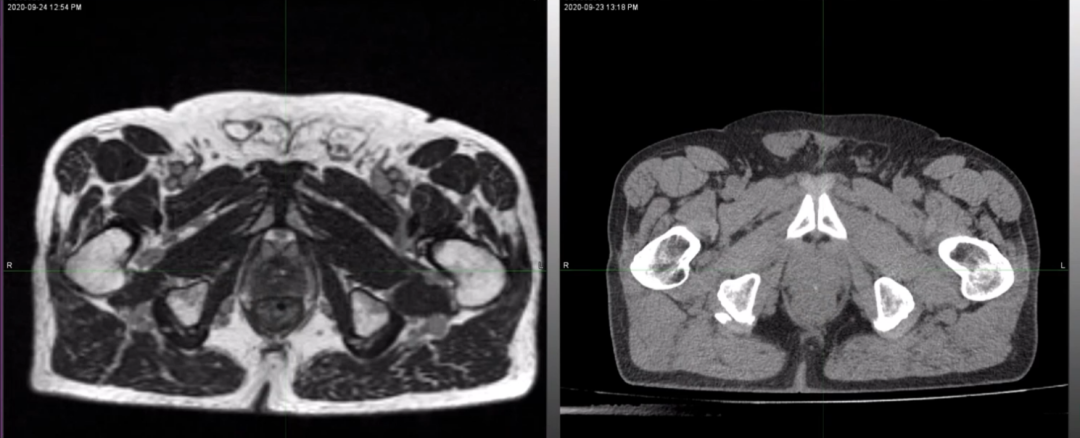

ÁíÍ⣬£¬£¬£¬£¬£¬£¬Dr. Camilleri»¹Õ¹Ê¾ÁËһλ÷ÅÊàŦÖû»ÊõºóǰÏßÏÙ»¼ÕßMRIdian 0.35T MRIÓ°ÏñºÍCT¶¨Î»Í¼Ïñ£¬£¬£¬£¬£¬£¬£¬MRIdian MRIͼÏñÊܽðÊô÷ÅÊàŦ¼ÙÌåÓ°Ïì½ÏС£¬£¬£¬£¬£¬£¬£¬ÈÔÄÜ¿´Çå°ÐÇøºÍËùÓÐΣ¼°Æ÷¹Ù£¬£¬£¬£¬£¬£¬£¬¼ûFigure 5¡£¡£¡£¡£¡£¡£ÒÔÊÇ£¬£¬£¬£¬£¬£¬£¬ÈÔÈ»ÄÜΪ»¼ÕßÌṩÖðÈÕÔÚÏß×Ô˳Ӧ·ÅÁÆÍýÏ룬£¬£¬£¬£¬£¬£¬µ«ÖµµÃ×¢ÖØµÄÊÇ£¬£¬£¬£¬£¬£¬£¬ÉäÊø±ØÐè±Ü¿ª½ðÊô÷ÅÊàŦ£¬£¬£¬£¬£¬£¬£¬¼ûFigure 6¡£¡£¡£¡£¡£¡£

Figure 5?Dr. CamilleriչʾµÄ÷ÅÊàŦÖû»ÊõºóǰÏßÏÙ»¼ÕßMRIdian 0.35T MRIÓ°Ïñ£¨×󣩺ÍCT¶¨Î»Í¼Ïñ£¨ÓÒ£©£¬£¬£¬£¬£¬£¬£¬MRIdian MRIͼÏñÊܽðÊô÷ÅÊàŦ¼ÙÌåÓ°Ïì½ÏС